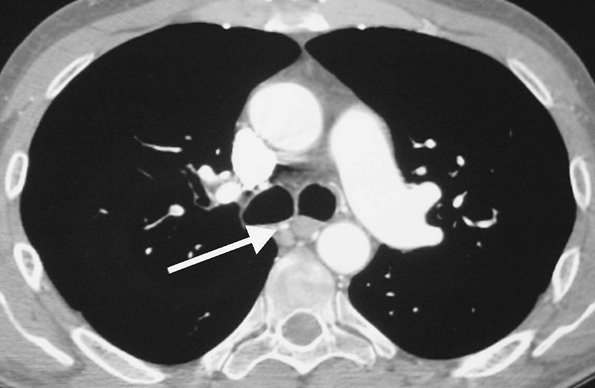

FIGURE 17-7. Acute PE. CTPA of a 76-year-old man with acute shortness of breath shows a large intraluminal filling defect within the proximal right lower lobe pulmonary artery (solid arrow) and a smaller intraluminal filling defect within a segmental pulmonary artery to the left lower lobe (dashed arrow).